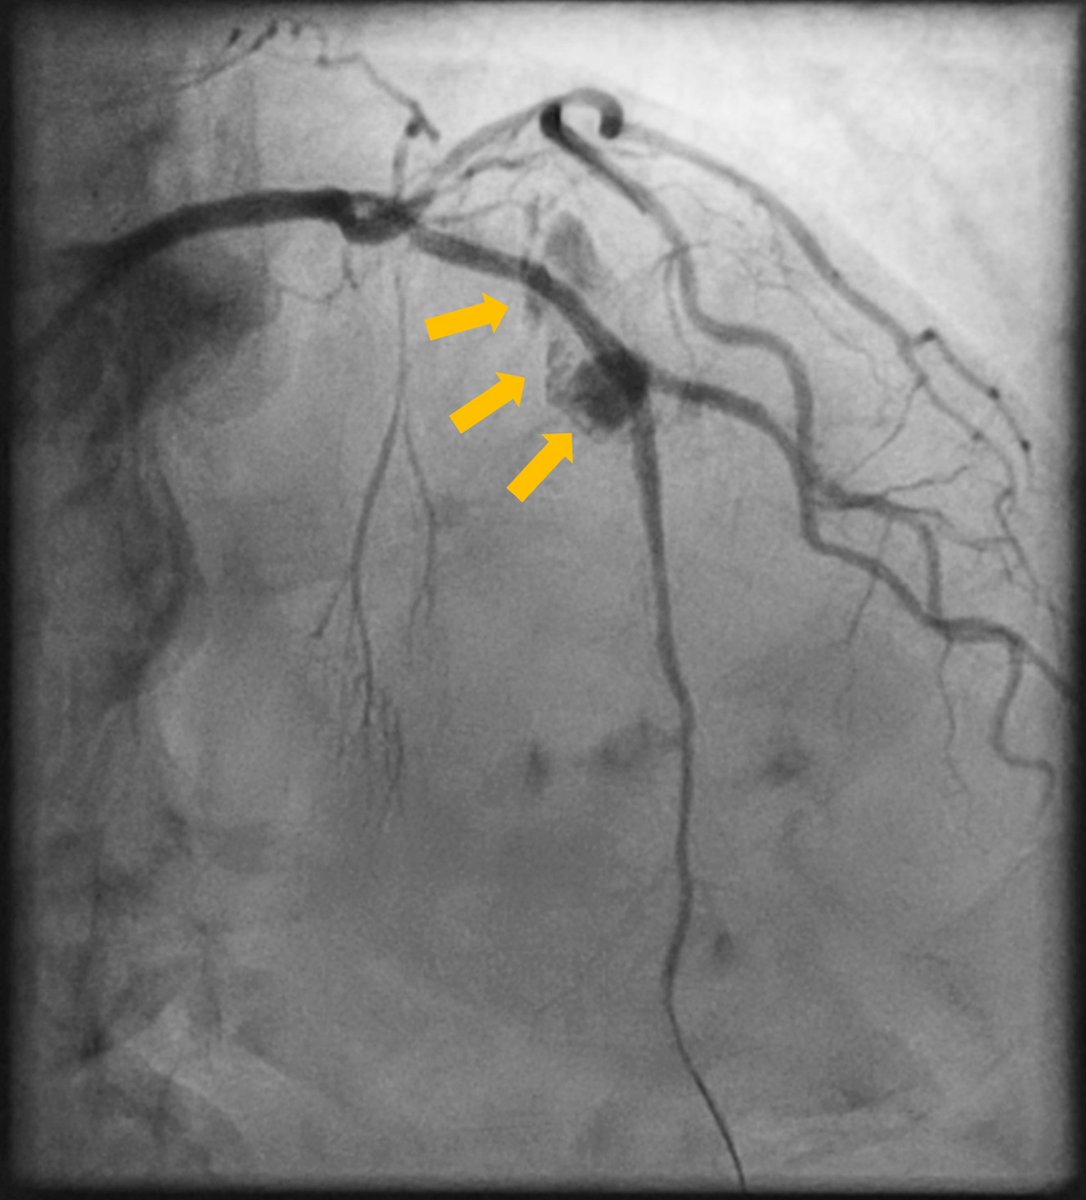

@EmilHolckMD

🔥 First-in-human report: Treatment t of a coronary bifurcation core perforation with dual covered stents! Take-home 🥽 Prepare in the wet lab 🫀 Complex PCI techniques can be needed in ACS patients 🚨 Stepwise bifurcation treatment was key! https://t.co/GXmlWxJBzC